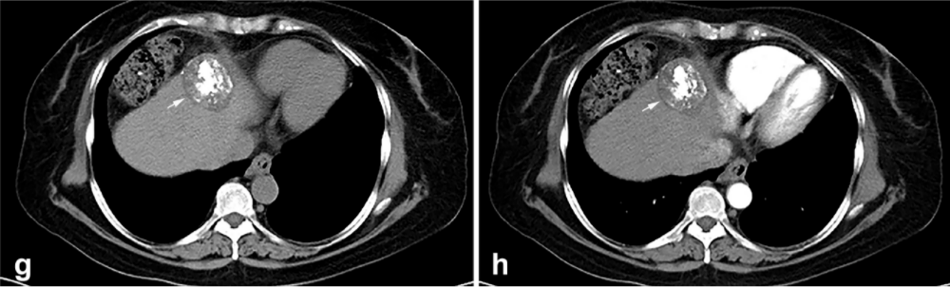

背景:由于一些原因,位于膈肌附近的腫瘤的熱消融在技術(shù)上具有挑戰(zhàn)性。首先,術(shù)中計(jì)算機(jī)掃描和超聲檢查無法清晰顯示射頻消融/微波消融切緣。第二,消融過程中不利的針分布和過熱可能導(dǎo)致肝包膜破裂,并對(duì)膈、肺和心臟造成嚴(yán)重?fù)p傷。第三,即使使用人工腹水,仍有9~22%的患者因肝周粘連或腫瘤位置靠近肝表面而導(dǎo)致膈肌熱損傷。冷凍消融可能是毗鄰膈肌的HCC的一種有前途的治療方法,因?yàn)樵谙谶^程中使用CT和US可以很好地顯示腫瘤邊緣。盡管一些研究評(píng)估了在高危區(qū)域使用冷凍消融治療HCC,但很少有研究針對(duì)膈肌臨近區(qū)域。

背景:肝癌是中國最常見的惡性腫瘤之一,發(fā)病率和死亡率都很高。雖然手術(shù)切除是最好的治療方法,但大多數(shù)患者處于晚期或直到住院才有手術(shù)指征。對(duì)于單個(gè)腫瘤直徑小于5厘米的患者,微創(chuàng)治療與手術(shù)切除效果相當(dāng);多個(gè)病灶小于3個(gè),單個(gè)病灶最大直徑小于3cm;不侵犯血管、膽管、鄰近器官和遠(yuǎn)處轉(zhuǎn)移。雖然一些傳統(tǒng)消融技術(shù)方式可以使部分患者受益,但不適用于特殊部位肝癌(定義為毗鄰大血管、肝外臟器和重要結(jié)構(gòu)的腫瘤)的治療。冷凍消融作為一種相對(duì)較新的治療方式,具有明顯的冰球效果、療效好、激活抗腫瘤免疫、并發(fā)癥發(fā)生率低等優(yōu)點(diǎn),尤其適用于特殊部位肝癌患者的治療。我們的研究目的是探討CA治療特殊部位肝癌的安全性、可行性和有效性。

① 在我們的研究中,技術(shù)成功率為100%。動(dòng)態(tài)增強(qiáng)MR檢查隨訪1個(gè)月,66例患者首次技術(shù)有效率為65例(98.5%),MR影像學(xué)未發(fā)現(xiàn)外周臟器損傷。中位隨訪時(shí)間14個(gè)月(范圍2-28個(gè)月)。高危部位肝癌局部腫瘤進(jìn)展率曲線:6、9、15和24個(gè)月的累積局部腫瘤進(jìn)展率分別為10.2%、16.5%、20.9%和30.5%。